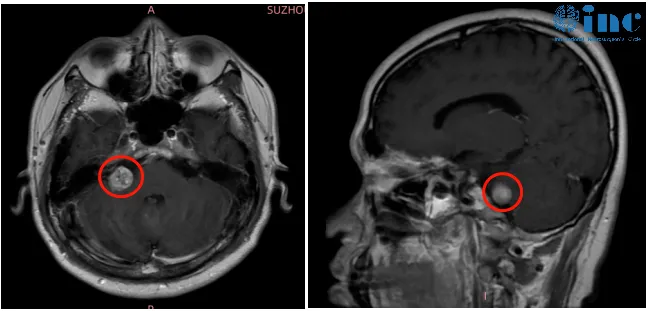

术后,李女士恢复顺利。虽因水肿出现过短暂面瘫,但半年后面部功能完全恢复。术后两年复查MRI,肿瘤无任何复发迹象,面部功能良好。